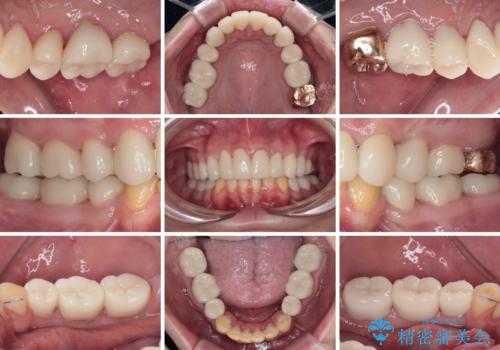

- 一時期の拒食症に伴い歯が酸で溶けてボロボロになってしまったとのことで来院された患者様です。

酸によりエナメル質の大半が溶けており、下顎前歯以外は酷いむし歯のような状態でした。

途中来院が困難な時期があったり、歯周外科処置を行って治癒を待ったりと、治療期間は長くなりましたが、初診時とは比べものにならないくらいきれいに仕上げることができました。